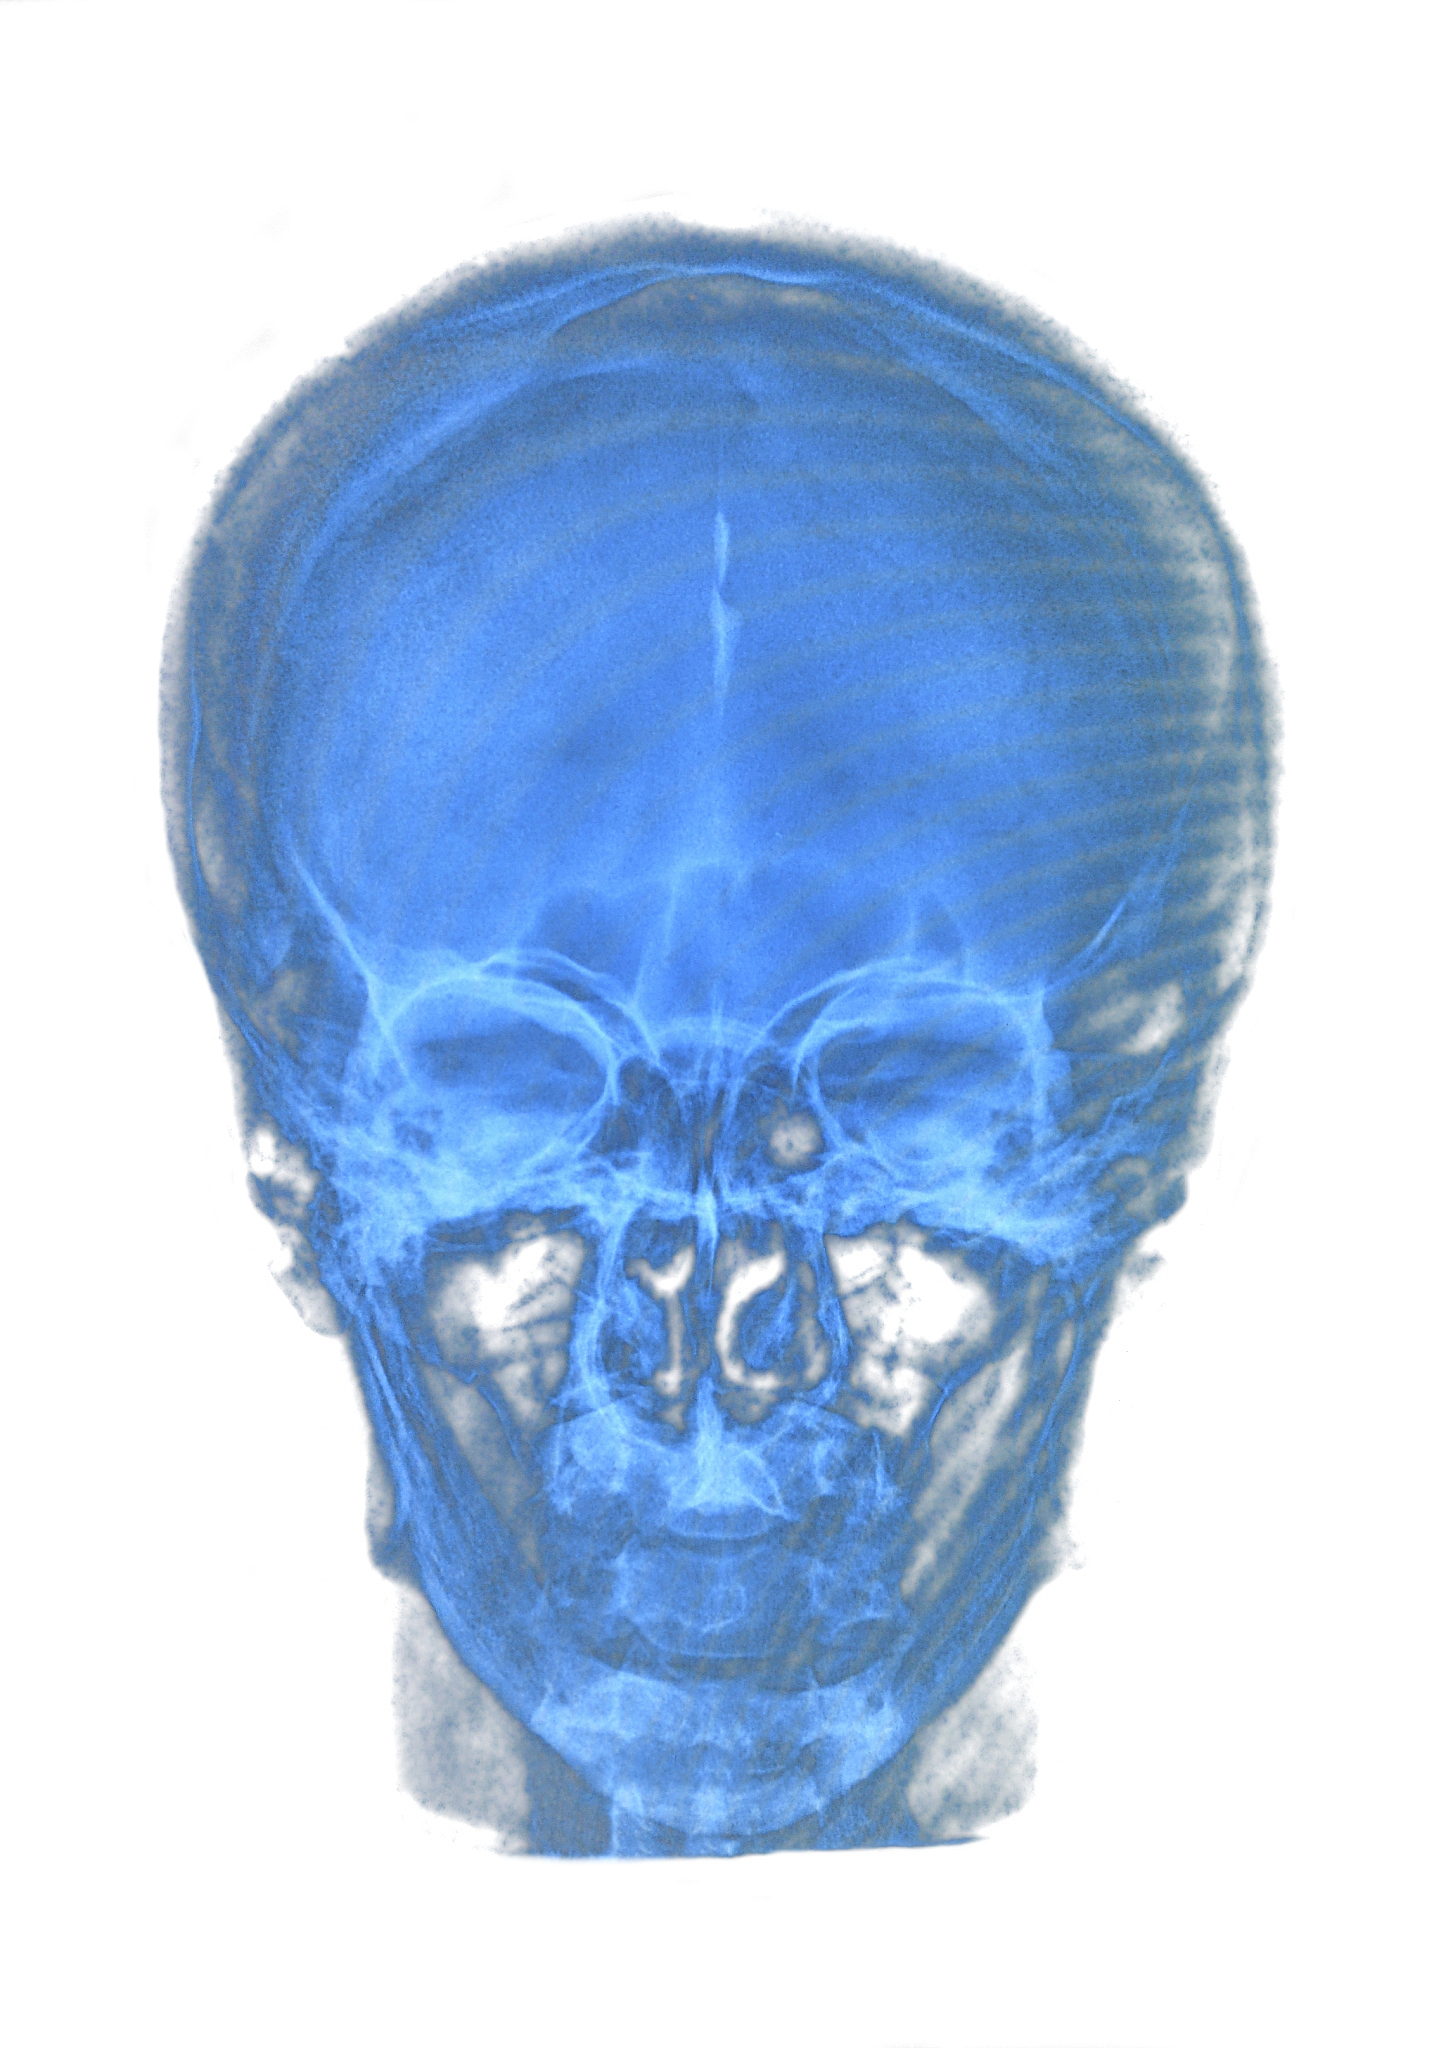

医学影像学是一门涉及医学、物理学、计算机科学等多学科交叉的学科,其研究内容包括医学影像的获取、处理、分析、诊断和治疗等方面。医学影像学技术已成为现代医学诊断和治疗的重要手段,为医学研究和临床实践提供了强有力的支持。

医学影像学的主要研究内容包括医学影像的获取、处理、分析、诊断和治疗等方面。医学影像学技术已成为现代医学诊断和治疗的重要手段,为医学研究和临床实践提供了强有力的支持。在第三军医大学医学影像学专业中,学生将学习医学影像学的基本理论和技术,包括医学影像学的物理学基础、医学影像学的图像处理和分析技术、医学影像学的临床应用等方面。

医学影像学专业是一门涉及医学、物理学、计算机科学等多学科交叉的学科。医学影像学的主要研究内容包括医学影像的获取、处理、分析、诊断和治疗等方面。在医学影像学的研究和应用中,医学影像学的技术已成为现代医学诊断和治疗的重要手段,为医学研究和临床实践提供了强有力的支持。